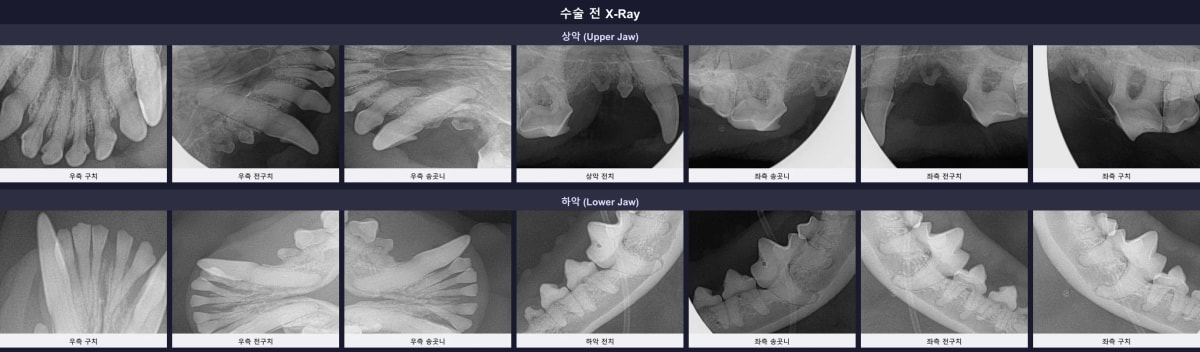

수술 전 전체 구강 방사선 검사 (X-ray) 이미지

이어지는 디지털 구강 엑스레이 검사에서도 좌측 상악 어금니(206번)와 좌측 하악 송곳니(303번) 주변의 잇몸뼈가 뿌리 끝부분까지 심하게 녹아내린 치조골 흡수(ABL3) 소견이 관찰되었습니다. 이미 주변 조직의 지지력을 상실하여 회복이 불가능한 상태였습니다.